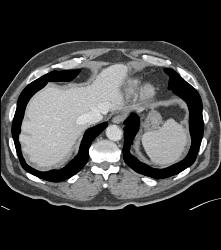

Renal Cell Carcinoma Metastatic to the Heart -right Atrium and Ventricle